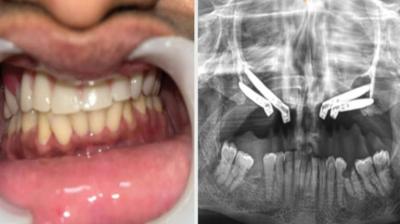

24 वर्षीय युवती के चेहरे पर लौटी मुस्कान और आत्मविश्वास

6 Sep, 2025 10:00 PM IST | MEDICALLIFE.IN

एम्म में जटिल सर्जरी को सफलतापूर्वक अंजाम दिया है। इस सर्जरी में ट्यूमर के कारण काटे गए निचले जबड़े को पैर की हड्डी से दोबारा बनाया गया और उसमें 13...